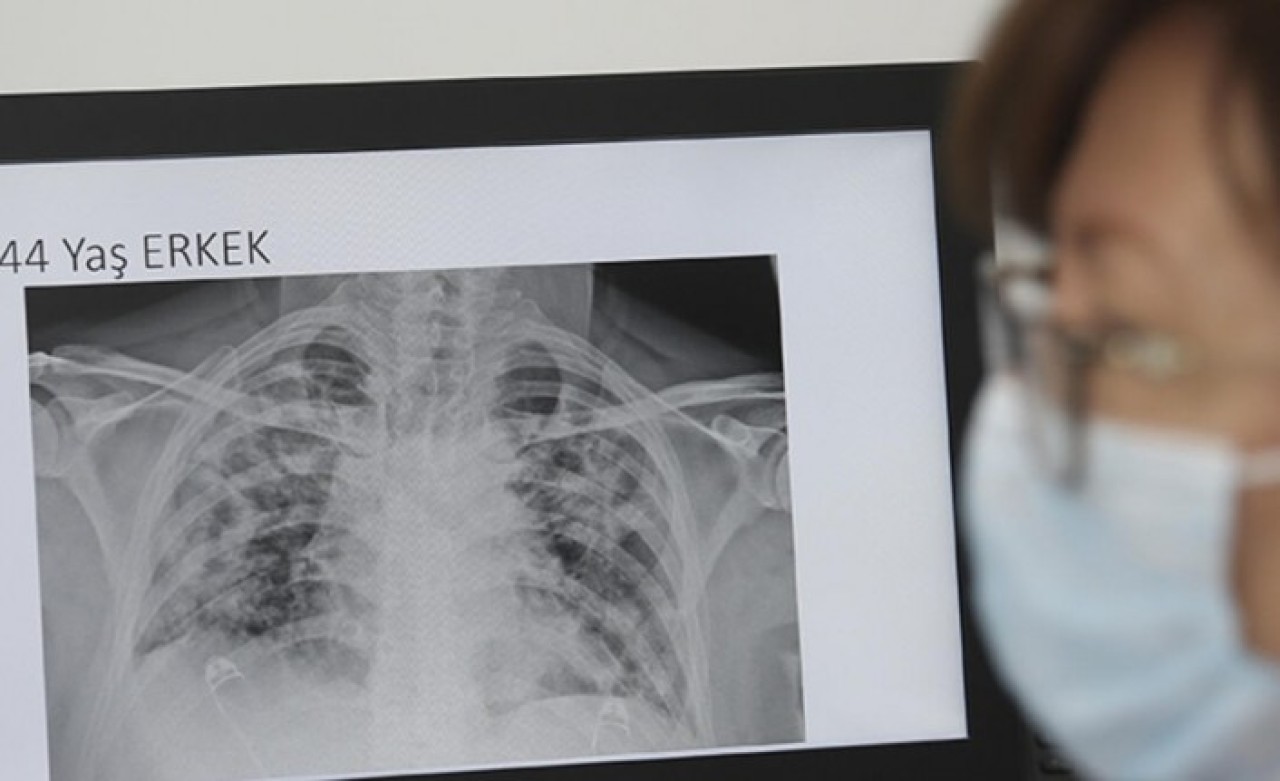

Sözcü'nün haberine göre, bilim insanının paylaştığı röntgen sonuçları dikkat çekti. Soldaki görselde sigara içen bir bireyin akciğer filmi görülürken sağda ise koronavirüsü yenmiş bir bireyinki yer alıyor. Akciğer filminde siyahlar ne kadar fazlaysa o kişinin ciğer kapasitesi ve sağlığı o kadar iyi anlamına gelir. Beyazlığın artması akciğerin kapasitesinin azaldığı anlamına gelir.

Röntgen sonuçlarında koronavirüsü geçirmiş ve sağlığına kavuşmuş kişilerin ciğerlerindeki hasarın sigara tiryakilerinden çok ama çok daha kötü olduğunu gösteren Bankhead-Kendall, “Sağlıklı bir bireyin röntgen sonucunda siyah alan büyük olur. Bu da o kişinin ciğerlerine alabileceği oksijen seviyesini gösterir. Sigara içenlerde hafif hareler yer alırken Covid-19 hastalarının ciğerleri ise bembeyazdır. Yani bu da koronavirüsü yenenlerde bile akciğer sorunları yaşanabildiğini gösteriyor” dedi.

Bankhead-Kendall, kıyaslama yapmak için sağlıklı bir bireyin akciğer filmini de paylaştı.